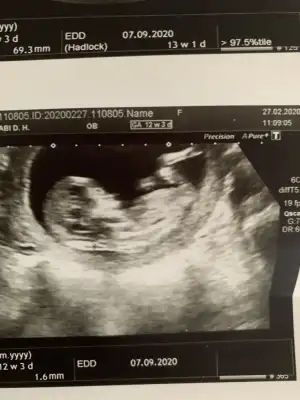

dr soylemeden siz gorun genital nub teorisi ( bebegin cinsiyeti)

Senin nubu çizdim cnm arkadaşında çizdim pipide vardı arkadaş pipi olsa söylemezmi deyince bende diğer 10 ve 11 haftasndaki tahminim devam dedim çok istiyordu pipiyi dr görmedi deyince ne kadar geç ögrenise dedim yoksa baya baya pipiydi çizdiğim usg 😊 seninkinide çizdim parelel görünüyor tabi pozisyonu nubu bazen değiştiyor. umarım 31 yanlış tahminim var arasında olmazsın onlar beni yanıtan usgler 😊

Merhaba detaylıda kız dedi doktor, anketi doğru tahmin olarak işaretledim. Teşekkürler😁

Saglıkla gelsin prenses 😊😊 ilk kız dedim teyit etmek için başka usg istemiştim. Teşekkurler dönüşler için 😊